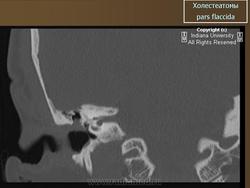

Диагностика холестеатомы представляет определенные трудности. Основными методами выявления холестеатомы последние несколько десятилетий остаются отоскопия (отомикроскопия) и рентгенологические методы (рентгенография в различных укладках и компьютерная томография). Компьютерная томография височных костей позволяет диагностировать холестеатому намного чаще, чем обычная рентгенография, однако степень достоверности данной диагностики остается невысокой, так как плотность холестеатомы практически соответствует плотности грануляционной ткани. Поэтому чувствительность метода КТ в диагностике холестеатомы составляет всего 71% при специфичности 55% [50]. Кроме того, следует учитывать, что указанный метод требует не только дорогостоящего оборудования, но и высококвалифицированных рентгенологов со специальной подготовкой, позволяющей им правильно интерпретировать полученные результаты.

2. Применение компьютерной томографии позволяет повысить степень обнаружения патологического процесса до 90% случаев, однако не позволяет достоверно дифференцировать холестеатому и грануляционную ткань по причине низкой специфичности метода (55%).

ID: 5467 Cholesteatoma - acquired Dr Frank Gaillard - 26 Jan 2009 CT through the temporal bone demonstrates a soft tissue mass in Prussak'...